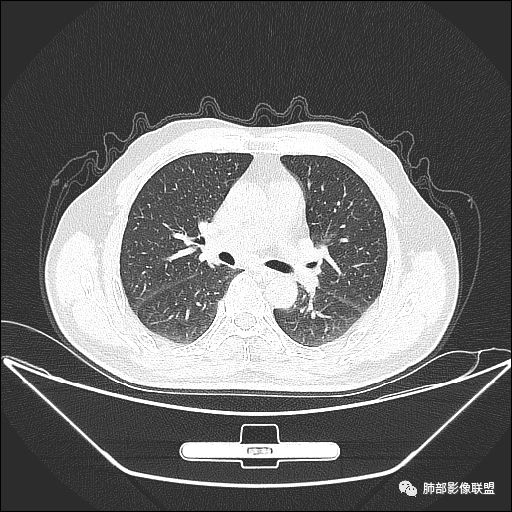

老年男性,亚急性病程,咳嗽咳痰。右肺中叶团片影,外朝内分布,大部分边界清楚平直,内侧支气管进入,团片影见低密度坏死区,强化明显,延迟强化,血管破坏不明显,符合爬行征5个特点:

1.肺外周生长。

2.外侧部分体积大于内侧。

3.病变最大径与肺的纵轴及水平面任何一条轴线不平行。

4.病变内侧支气管通畅。

5.病变区域肺容积无缩小。

双侧肺门及纵隔淋巴肿大并可见钙化。考虑结核,但部分边缘膨隆,肿瘤待排。

主病灶在中叶,但是左肺舌段叶有条索影,陈旧病变。蓝色箭头支气管受压,是淋巴结肿大

主病灶在中叶,但是还有结节状病变在下叶

这个支气管是走形通畅,但是壁增厚的。比较符合炎症改变

下面我们看看支气管都在吗?

内侧段是通畅但是受压的

外侧段一开始狭窄

但是远端通畅,所以我认为支气管都没有堵塞,不太可能是鳞癌

边缘还有多发小灶

淋巴结肿大,钙化。

但是钙化,密度高,没有融合,平扫没有坏死

病灶明显平直,中央是粘液栓,低密度,分界清楚

综上,考虑炎症,结核。